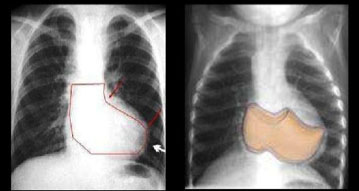

In the chest X-ray, the cardiac silhouette is normal or small with a raised cardiac apex and a reduced pulmonary arterial cone (resulting in a clog-shaped heart, see next image). The pulmonary vascularization is either normal or diminished.

The diagnosis is made with a chest X-ray, in addition to the clinical suspicion (fever with precordial pain which is exacerbated when lying face-up and sometimes auscultation of a pericardial friction rub). The X-rayshows cardiomegaly and the echocardiogram, which is usually the best diagnostic tool, confirms the existence of an abnormal quantity of fluid in the pericardial cavity.